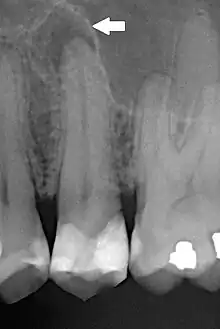

| Periapical dental radiograph showing chronic periapical periodontitis on the root of the left maxillary second premolar. Note large restoration present in the tooth, which will have undergone pulpal necrosis at some point before the development of this lesion. | |

Periapical periodontitis or apical periodontitis[1] (AP) is an acute or chronic inflammatory lesion around the apex of a tooth root, most commonly caused by bacterial invasion of the pulp of the tooth.[2] It is a likely outcome of untreated dental caries (tooth decay), and in such cases it can be considered a sequela in the natural history of tooth decay, irreversible pulpitis and pulpal necrosis. Other causes can include occlusal trauma due to 'high spots' after restoration work, extrusion from the tooth of root filling material, or bacterial invasion and infection from the gums. Periapical periodontitis may develop into a periapical abscess, where a collection of pus forms at the end of the root, the consequence of spread of infection from the tooth pulp (odontogenic infection), or into a periapical cyst, where an epithelial lined, fluid-filled structure forms.

The radiographic features of periapical inflammatory lesions vary depending on the time course of the lesion. Because very early lesions may not show any radiographic changes, diagnosis of these lesions relies solely on the clinical symptoms. More chronic lesions may show lytic (radiolucent) or sclerotic (radiopaque) changes, or both.